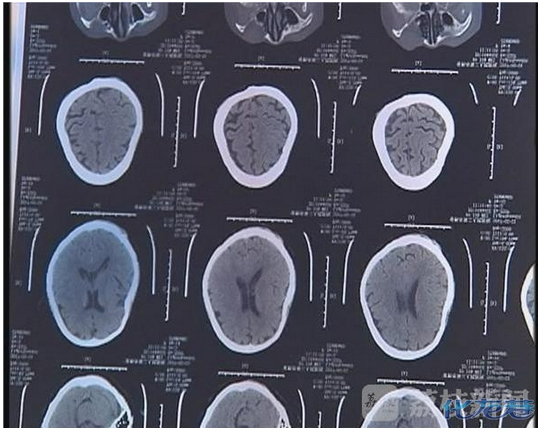

经医生诊断,徐金妹十一根肋骨被打断,左耳耳膜穿孔,全身多处软组织损伤。徐金妹说,当天被大儿子暴打后,她一度晕厥,而她的大儿子就用冰冷的井水将她浇醒。